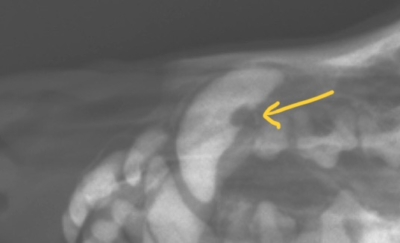

基礎疾患がありシニアの子ではありましたが、歯周病は経過観察しても治るというものではありません。別日に全身麻酔下で歯科レントゲン、口腔内精査を行い歯石除去、抜歯などを検討しました。術前検査の頭部レントゲン検査では、上顎犬歯に欠損があることもわかりました。こちらも手術中に確認することとしました。

頭部レントゲン

先ほどの頭部の拡大図。黄色矢印の位置で犬歯に一部虫歯のような欠損部が。